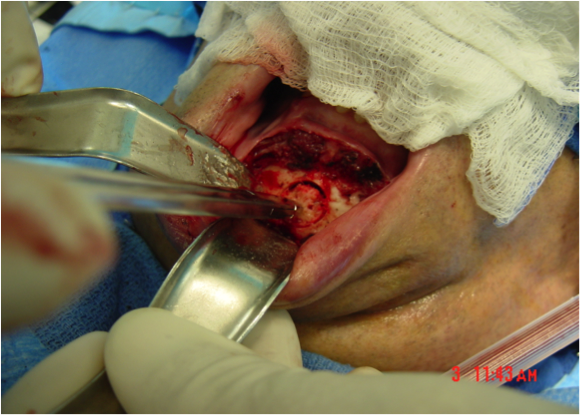

This procedure places tension on the tongue, limiting the posterior from shifting during sleep. The procedure starts with a small incision made inside the lower lip. Then, the surgeon moves away all the soft tissue to expose the lower jaw. Small rectangular cuts are then made in the lower jaw directly in front of the lower front teeth. This area attached to the genioglossus muscle is then moved forward and turned slightly. To hold this bone fragment in place, the surgeon puts in a titanium screw to immobilize it.

The photos on this website are from real surgeries performed by Dr. Ulloa. Due to the

graphic nature of the images and content, viewer discretion is advised.